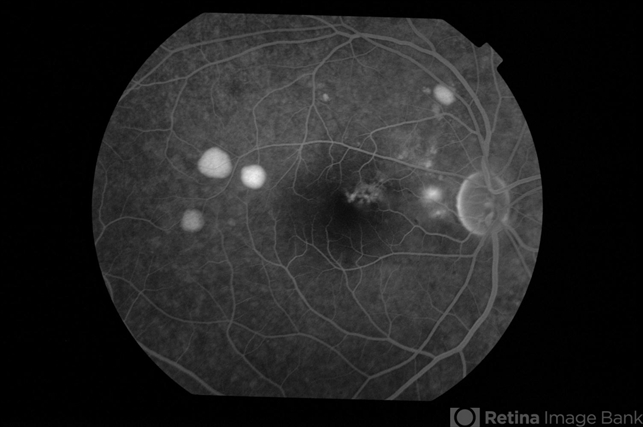

- Bilateral Central Serous Chorioretinopathy

- central serous chorioretinopathy (CSCR)

- Late phase fluorescein angiogram of right eye of a 33-year-old gentleman with bilateral CSC.